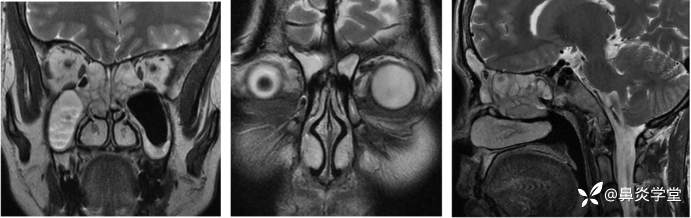

嗅通路 MRI:双侧嗅球、嗅束形态及信号未见明显改变,嗅三角区未见明显肿块。双侧梨形区、边缘。下丘脑未见明显形态及信号改变。附见:全组副鼻窦炎。

此外,该患者的症状以嗅觉减退为主,嗅通路 MRI 检查未见明显异常,排除嗅通路结构及嗅中枢功能异常,可进一步明确为鼻-鼻窦炎相关的嗅觉障碍[3]。